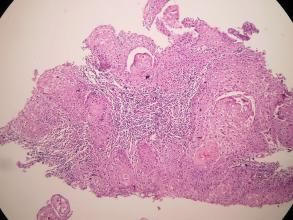

巨細胞型癌細胞團周圍常有多核巨細胞和炎症細胞浸潤。透明細胞型易誤認為轉移性腎腺癌。大細胞癌轉移較小細胞未分化癌晚,手術切除機會較大。